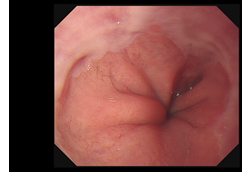

胃食道逆流反覆發作怎麼辦?

2022.07.01

食道功能檢查介紹